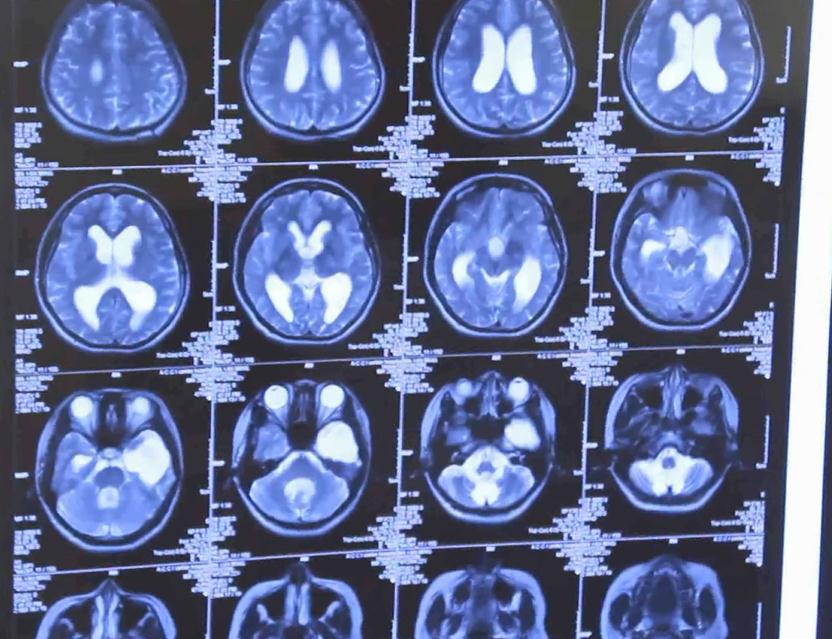

根据问诊情况和检查评估,确认小虹大脑颞叶部位放电异常,并且已经十五年的病史。“做脑电图发现她双侧放电都挺多的,而且一发作就是大发作,很严重。”,认为小虹情况符合手术指征。与病人家属沟通后,张教授为小虹实施了左侧颞叶标准切除术。手术历时七个小时,非常成功。

手术后检查一切正常

手术到现在一年多了,小虹恢复得特别好。再次给小红复查后介绍,癫痫也不发作了,大脑核磁复查也没什么问题,小姑娘精神态势也不错,效果还是比较理想的。小虹的父亲说:“之后没有发作过,现在挺好的,能自己自由行动,大人也不用跟着照看。”